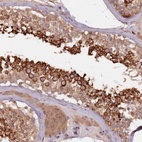

Immunohistochemical staining of human testis shows strong cytoplasmic positivity in cells in seminiferus ducts.